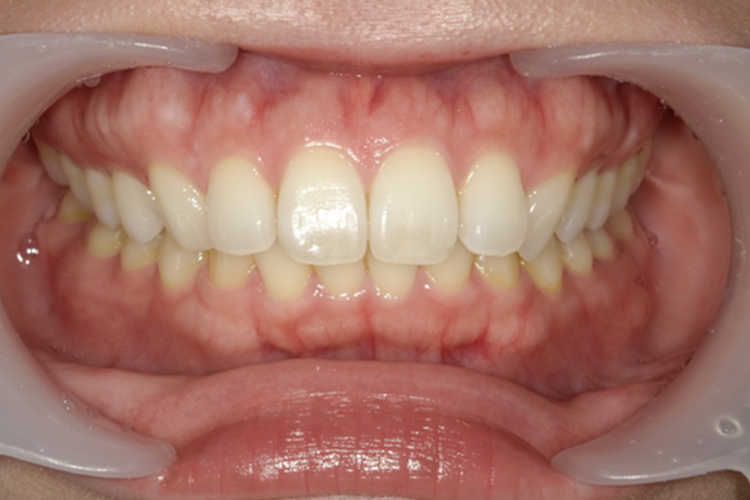

治療前

治療後